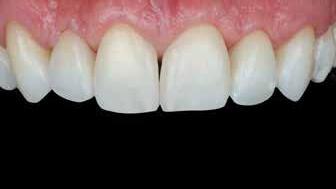

A fogászati kezelések során manapság már nem kizárólag az esztétikai megjelenés helyreállítására törekszünk. Sokszor a kedvezőtlen esztétikai megjelenés hátterében álló okok következményes módon a fogazat funkcionális működését is károsítják, így a kezelések során ezeknek a helyreállításával is foglalkoznunk kell. A különböző funkcionális és esztétikai diszkrepanciák kezelésére számtalan módszer létezik, ám ezen fogászati beavatkozások mindegyikében közös, hogy a kivitelezésük során nagyon szoros együttműködésre van szükség a kezelést végző fogorvos és a munkáját segítő fogtechnikus között. Az alábbi esetbemutatás során egy fiatal hölgypáciens fogazatának héjak alkalmazásával történő esztétikai és funkcionális rehabilitációját szeretnénk ismertetni.

1. és 2. ábra: A kiindulási és a befejezést követően látható állapot összehasonlítása extraorális felvételek segítségével.

Esetbemutatás

A 19 éves hölgypáciens azzal a kéréssel jelentkezett a rendelőnkbe, hogy szebb fogakat szeretne. Az első konzultáció alkalmával megkérdeztük, hogy mi zavarja leginkább a fogazatának jelenlegi megjelenésében, valamint azt is megbeszéltük vele, hogy milyen végeredmény elérése esetén lenne maradéktalanul elégedett. Ebben az esetben a kezelési célokat az alábbiakban határoztuk meg:

A páciens fogazata esztétikai megjelenésének és funkcionális működésének a lehető legtöbb, saját foganyag megtartása mellett történő helyreállítása (1. és 3. ábra). A lehető legideálisabb esztétikai végeredmény elérése érdekében néhány esetben a fogak alakjának módosítá -

sára is szükség van (2. és 4. ábra).